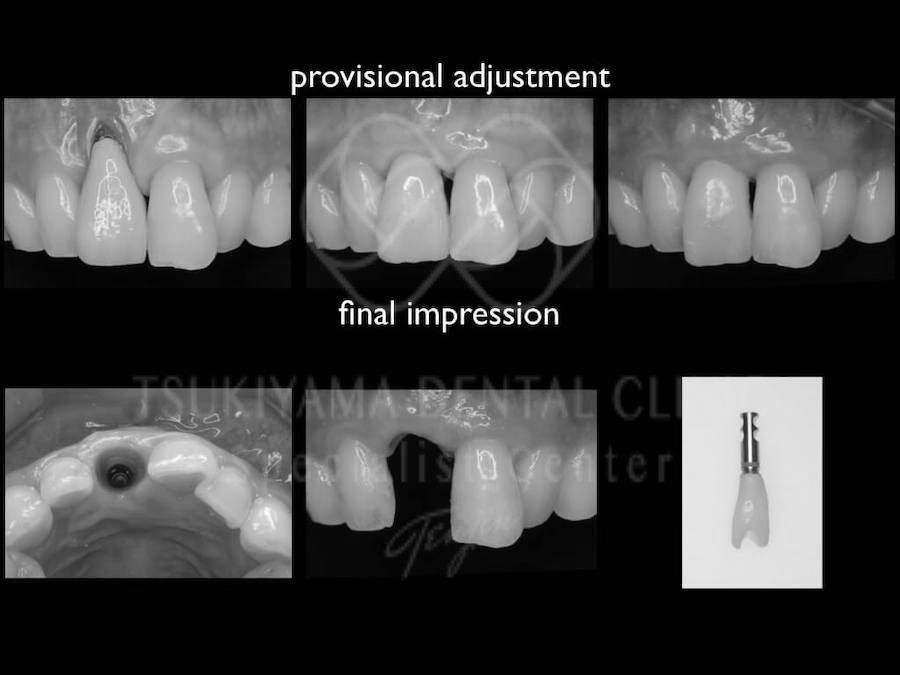

治療中